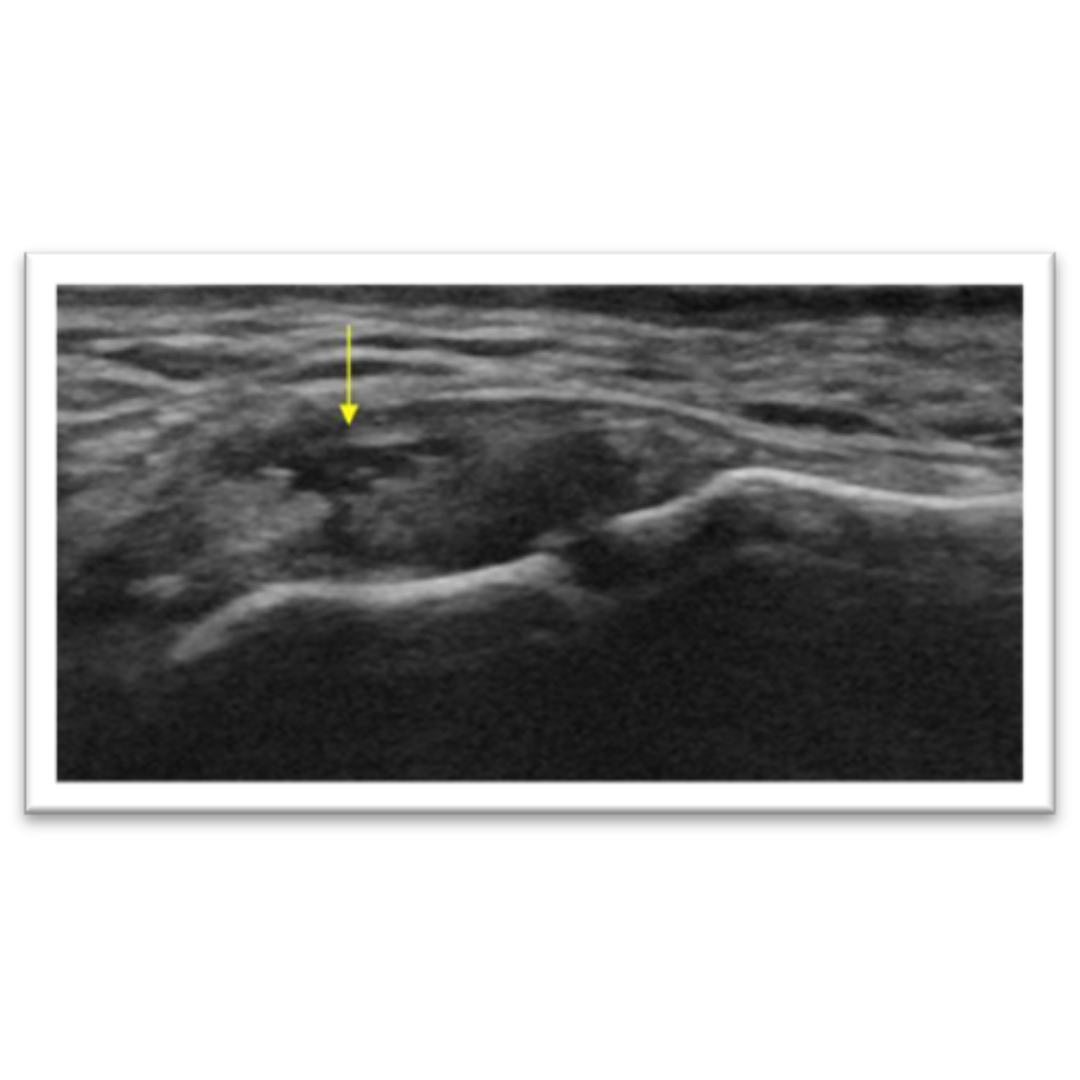

Rotura con avulsión

Se observan los signos de esguince sumado a imagen hiperecogénica puntiforme en porción proximal del ligamento compatible con fragmento óseo de la cabeza del Metacarpo, asociado a área hipoecogénica (flecha amarilla) sugerente de rotura parcial, no se evidencia una retracción significativa del ligamento.